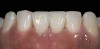

A patient in her 60s wanted to improve her smile but declined orthodontic treatment in favor of porcelain veneers (Figure 13). However, addressing her 8-mm pocket was the first step. The practitioner created biologically clean root surfaces using ultrasonic open-flap debridement, finishing burs, and manual tool instrumentation. Next, a mineralized freeze-dried bone allograft saturated in platelet-derived growth factor (Figure 14) using chemotaxis pulled the stem cells capable of regeneration into the site where repopulation was needed. Prior to closure, a resorbable membrane, polylactic acid-guided tissue regeneration—known for periodontal regeneration—was used (Figure 15). At 10 weeks, adequate healing had occurred. The patient at 6 and 10 weeks showed continued healing. Although some postoperative recession was evident, probing depths were less than 2 mm, and the patient was referred back to the restorative dentist for restorative therapy. As of this writing, she has not lost any teeth and is periodontally stable (Figure 16).

The final restorative situation. (Restorative therapy by Dr. B. Wilk, Chalfont, PA.)

Figure 16